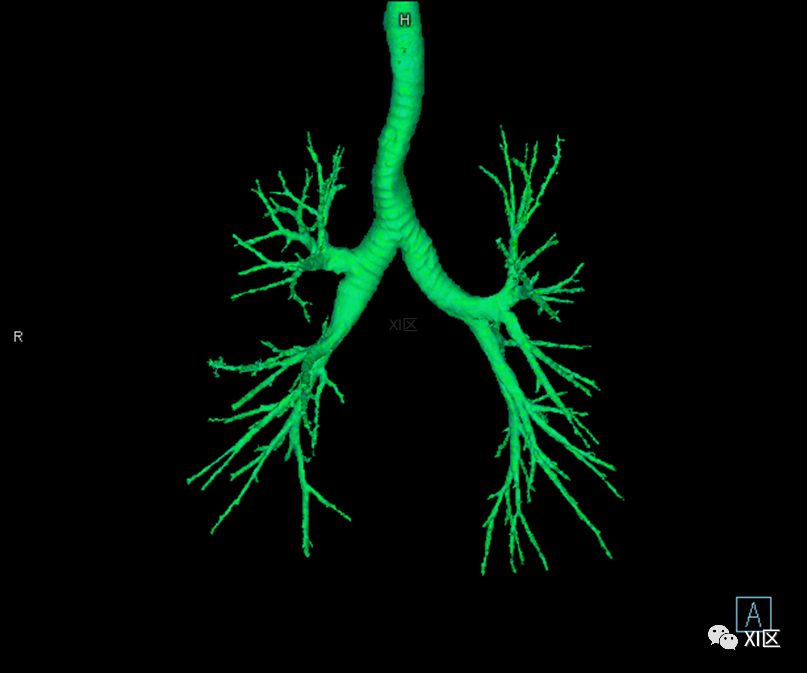

气管支气管树与两肺融合显示

气管树的解剖

人的支气管(第1级)至肺泡约有24级分支。支气管经肺门入肺,分为叶支气管(第2级),右肺3支,左肺2支。叶支气管分为段支气管(第3~4级),左肺8支、右肺10支。段支气管就是肺的分段的依据。段支气管反复分支为小支气管(第5~10级),继而再分支为细支气管(第11~13级),细支气管又分支为终末细支气管(第14~16级)。从叶支气管至终末细支气管为肺内的导气部。终末细支气管以下的分支为肺的呼吸部,包括呼吸细支气管(第17~19级)、肺泡管(第20~22级)、肺泡囊(第23级)和肺泡(第24级)。 医学百科网 | YxBaike.Com

气管支气管形如树状,因此也称气管支气管树。 医学百科网 | YxBaike.Com

气管树 医学百科网 | YxBaike.Com